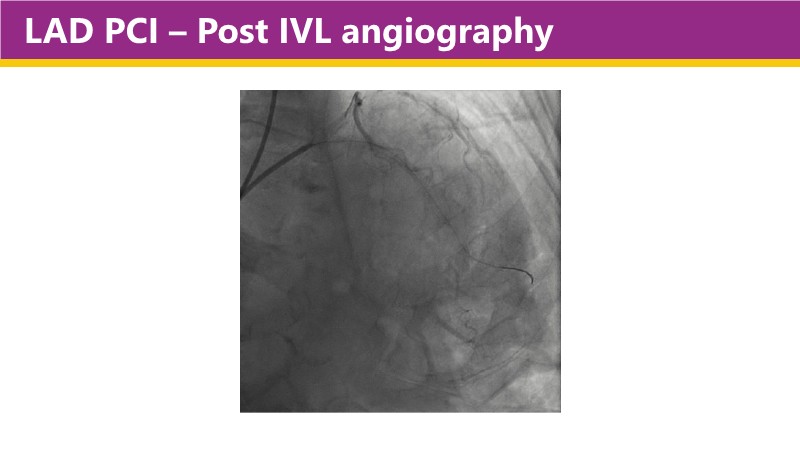

This EuroPCR 2025 session shares real-world insights confirming the promising results of the PINNACLE I trial, with LithiX IVL proving safe and effective across eccentric, concentric, and nodular calcifications.

Learn how this technology works, review the supporting evidence, and follow step-by-step case examples demonstrating optimal stent expansion and an efficient calcium modification workflow in daily practice.